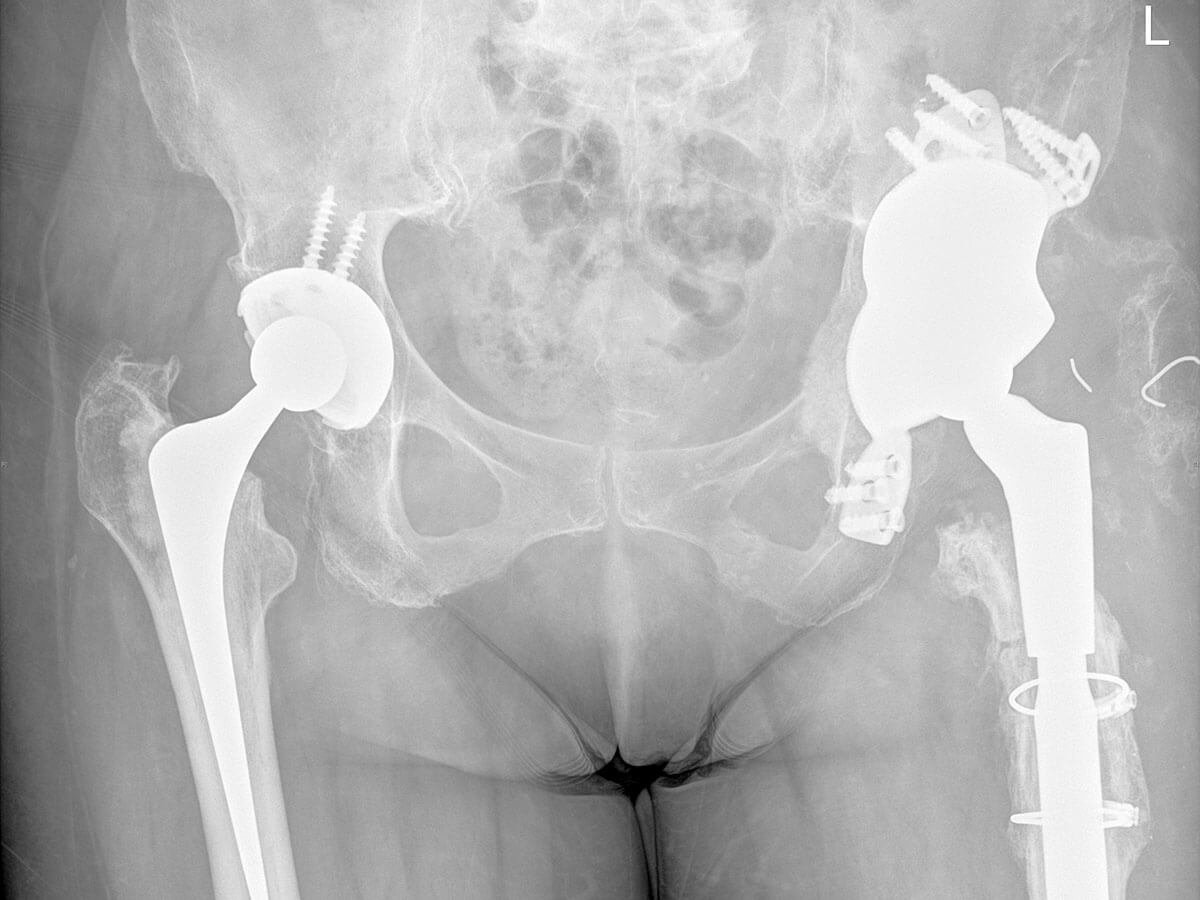

Revision Hip Replacement

Understanding the wear-and-tear changes that can affect your hip joint over time

Revision hip replacement surgery, also known as revision hip arthroplasty, is a complex procedure performed to address problems that can develop after a previous hip replacement. This may include pain, implant loosening, infection, dislocation, or wear of the prosthetic components. This page provides a detailed guide to help you understand what revision surgery involves, why it may be recommended, and what to expect before, during, and after the procedure. It is designed to equip you with clear, practical information and support as you prepare for surgery with Dr Jason Hockings.

Occasionally, a primary hip replacement may require revision due to persistent pain, implant wear, instability, loosening, fracture, or infection. Revision hip replacement surgery involves the careful removal and replacement of one or more components of the original hip prosthesis.

Depending on your individual condition, this procedure may also require the reconstruction of bone or soft tissue using bone grafts, augments, or specialised revision implants designed to restore stability and function. In cases of infection, a staged approach may be necessary, involving temporary spacers and antibiotic treatment before reimplantation.

Revision hip replacement is technically more complex than a primary procedure, requiring advanced surgical planning, careful handling of bone and soft tissues, and the use of specialised implants. Dr Jason Hockings has extensive experience in revision hip arthroplasty and will tailor your surgical plan to address your unique anatomy, diagnosis, and previous surgical history.

- X-rays: The most common starting point. These allow Dr Hockings to evaluate the alignment of the components, identify loosening, subsidence (sinking of the stem), fractures, or implant wear.

- CT scan: A 3D scan provides detailed images of bone and implant positioning, especially useful in cases where bone loss or structural changes are suspected.

Surgical options: Types of revision hip procedures

The type of revision hip replacement you may require depends on which part of the original prosthesis is failing, as well as the extent of bone loss, infection, or implant wear. Revision surgery is tailored to each patient and can range from minor adjustments to complete reconstruction of the hip joint.

The acetabular cup (socket) is removed and replaced. If there has been significant bone loss in the pelvis, bone grafts or specialised implants (such as augments or cages) may be used to rebuild the socket and provide stable fixation.

In cases where both the femoral and acetabular components are failing, a full revision may be required. This involves replacing the entire hip prosthesis and may include reconstructive techniques to address bone defects.

- The extent of bone loss - specialised implants such as modular femoral stems, dual mobility cups, revision acetabular components, or augment blocks may be used to restore joint stability and compensate for missing bone.